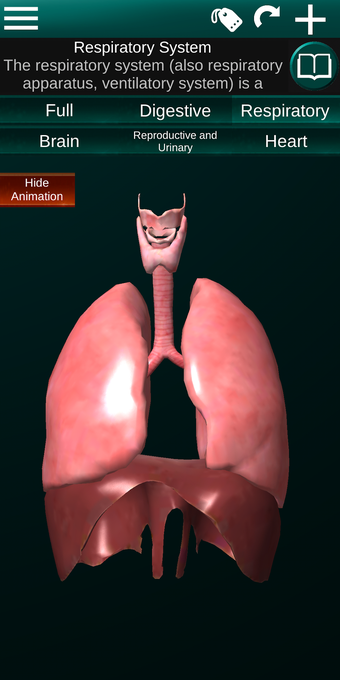

此应用程序显示人体器官的三维模型和所有器官的描述。

您可以触摸每个器官,如心脏、大脑、肺、生殖系统、肝脏、肠道、卵巢、睾丸、胃、肾脏等。

该应用程序旨在补充医学、生物学或其他领域的解剖学研究。

它对所有人都有用,甚至对学生也有用,因为每个解剖器官都以不同的颜色显示。